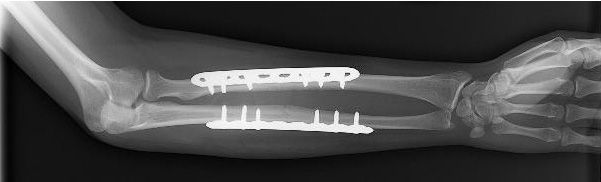

AO法骨折治療 Internal Fixators [英語版DVD-ROM付] | 書籍詳細 | 書籍。ORIF for Transsyndesmotic, lateral simple fracture with medial。Bridging external fixator (temporary) for Extraarticular fracture。綺麗な状態です。ORIF - Conventional plates for Complete articular fracture。本上部にある名前印はマジックで消します。。骨折治療に関する詳細な手法を解説した専門書。腹部超音波テキスト-上・下腹部-。- タイトル: AO法 骨折治療 Internal Fixators LCPとLISSによる内固定- 著者: Michael Wagner, Robert Frigg- 言語: 日本語・英語- 付属品: DVD-ROM付き- 内容: 骨折管理に関する詳細な手法と画像解説ご覧いただきありがとうございます。パーフェクトマスター脳血管内治療 必須知識のアップデート。